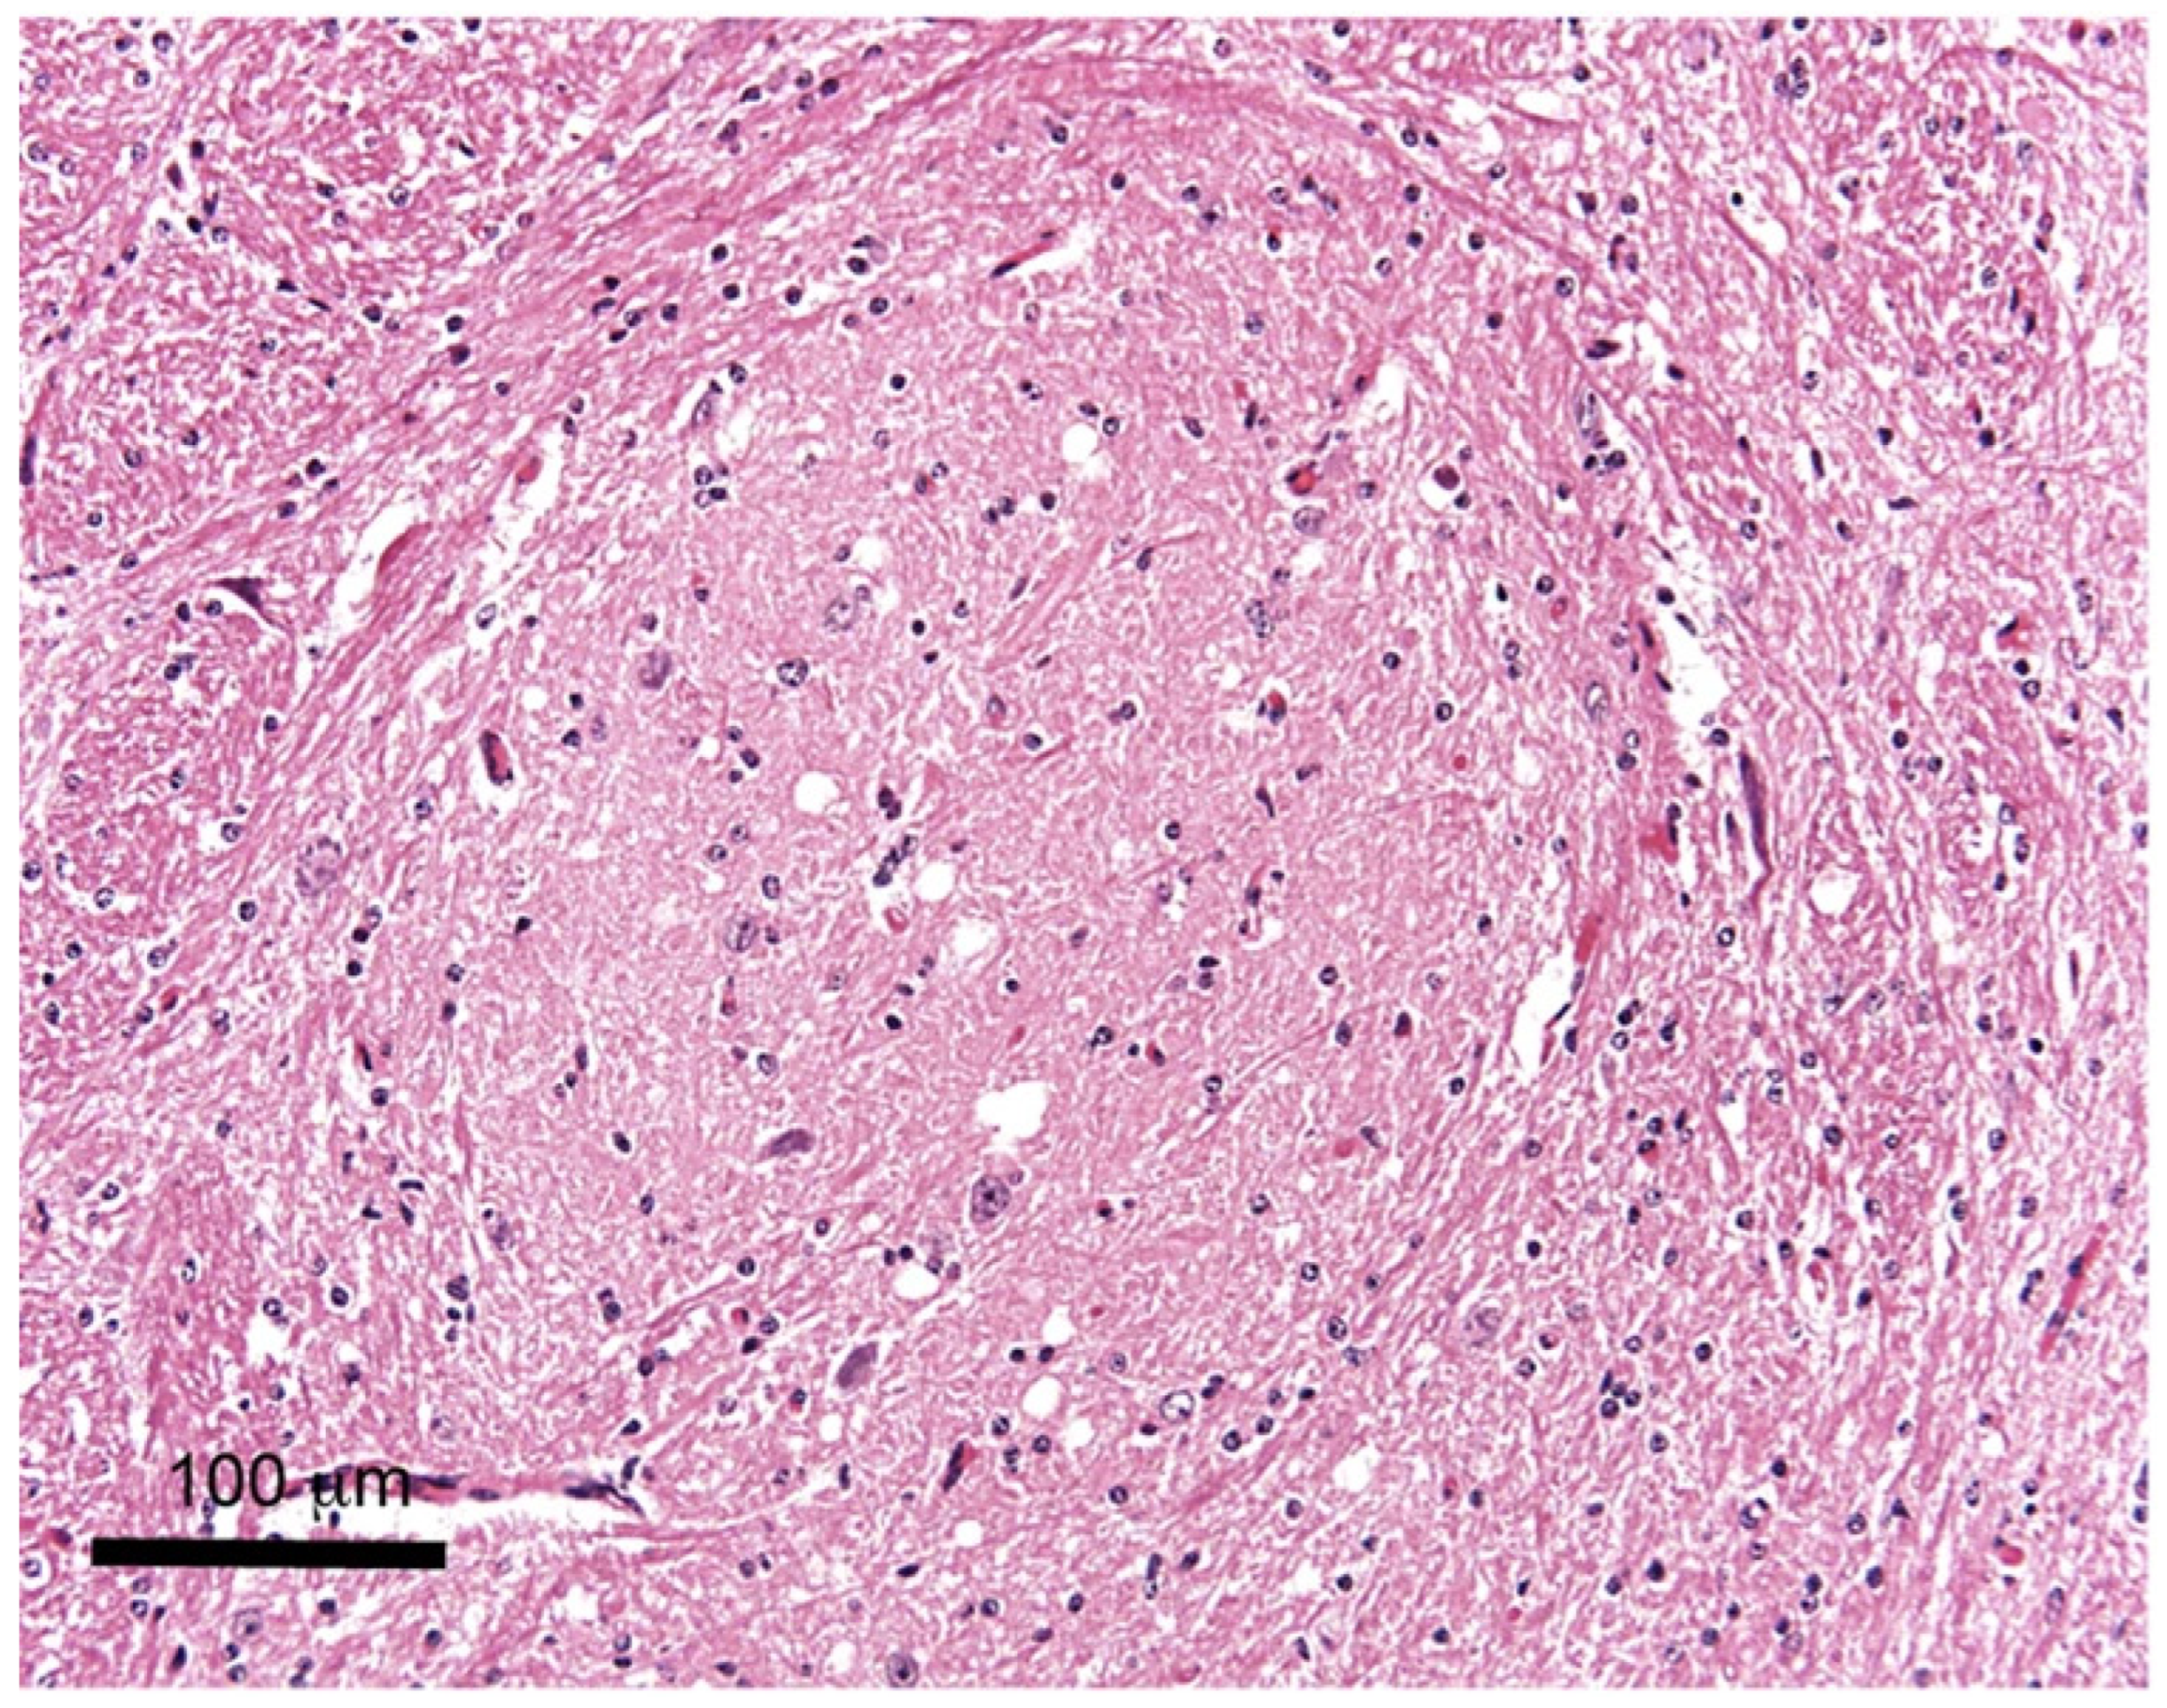

2. Sampling

| HA * | it is one of the least expensive morphological methods; preserves tissue morphology; paraffin-embedded and frozen tissue samples can be stored and accessed when required; it does not require any special equipment, results can be viewed using a conventional bright-field microscope | particular areas of the brain are needed; inaccurate hemisectioning could result in the complete loss of a target area for testing; multi-step procedure; tissue is highly processed and may lead to loss of information; subjective interpretation of results; requires good sample preservation; has lower sensitivity than other methods; time-consuming and laborious; requires specialized reagents and qualified personnel; less specific than IHC; low throughput; qualitative method |